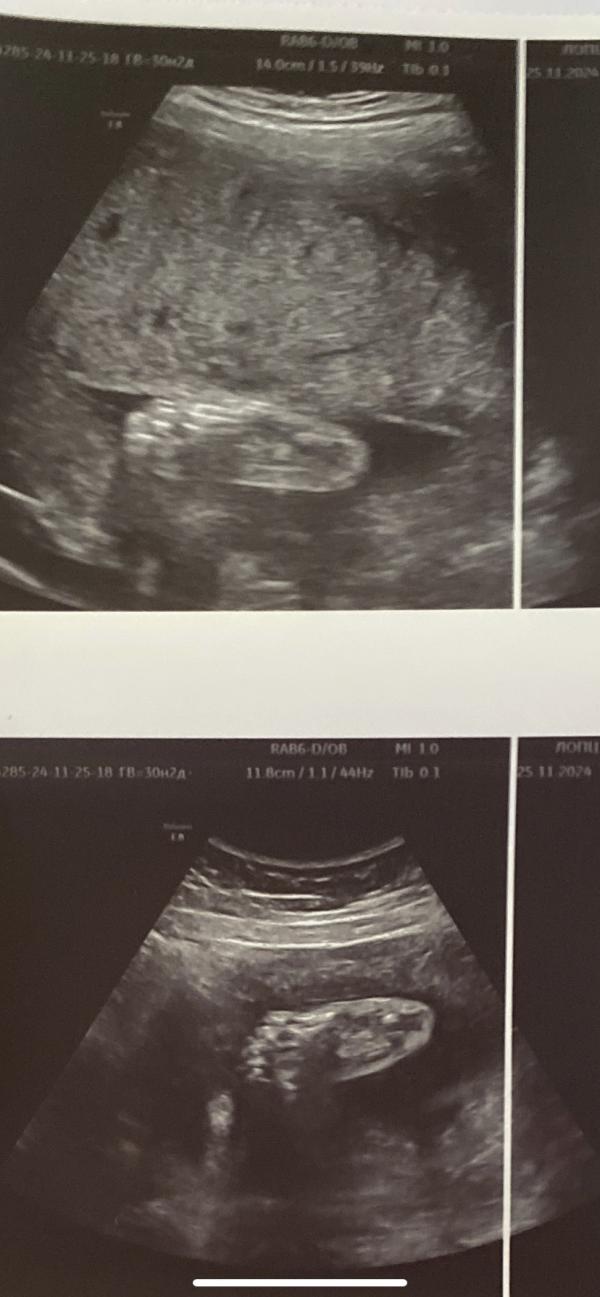

Монохориальная биамниотическая двойня 30 недель: вес мальчиков 1360 и 1370 грамм - все хорошо?

Монохориальная биамниотическая двойня

30 недель

Вес хороший у обоих мальчишек

1360гр и 1370гр

25.11.2024